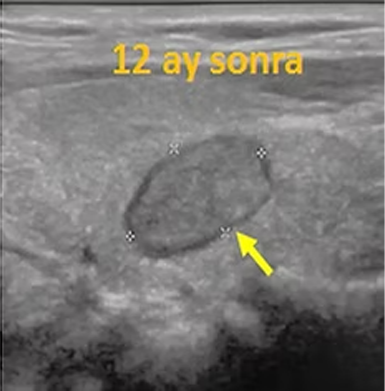

Alkol ablasyonu, günümüzde, kistik yani sıvı içeren iyi huylu tiroid nodüllerinde ilk seçilecek tedavidir. Solid (sıvı içermeyen) nodüllerde de başarılıdır, ancak alkolün nodülün her yerine yayılması için işlem deneyimli hekimler tarafından dikkatli olarak yapılmalıdır. Alkol ablasyonundan sonra nodül içindeki doku canlılığını kaybeder ve gittikçe küçülmeye başlar, bu küçülme aylarca devam eder.